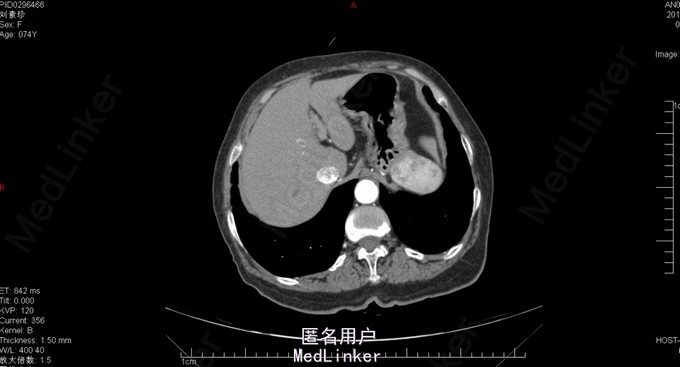

胆囊十二指肠瘘,结石性幽门梗阻

74岁女患,上腹部疼痛伴恶心呕吐3天。 3天前患者开始出现上腹部不适疼痛,同时伴有恶心、呕吐。呕吐物为胃内容物,餐后严重。患者在家自行消炎治疗,症状逐渐加重。患者为求进一步诊治来我院。 既往胆囊结石病史。

查体:上腹部压痛明显,伴反跳痛及肌紧张。 腹部ct:十二指肠内结石?(回忆部分)

胆囊十二指肠瘘,结石性幽门梗阻,腹膜炎。 给予患者胆囊切除+十二指肠修补局部引流?(记不太清)患者术后恢复还可以,顺利出院。

此病例为普外科轮转期间收集影像资料所得,病例内细致资料不全面,不能详尽分享。但此种病例少见,影像资料清晰,值得学习探讨。 欢迎普外专业同道探讨患者手术方式。让大家共同进步。